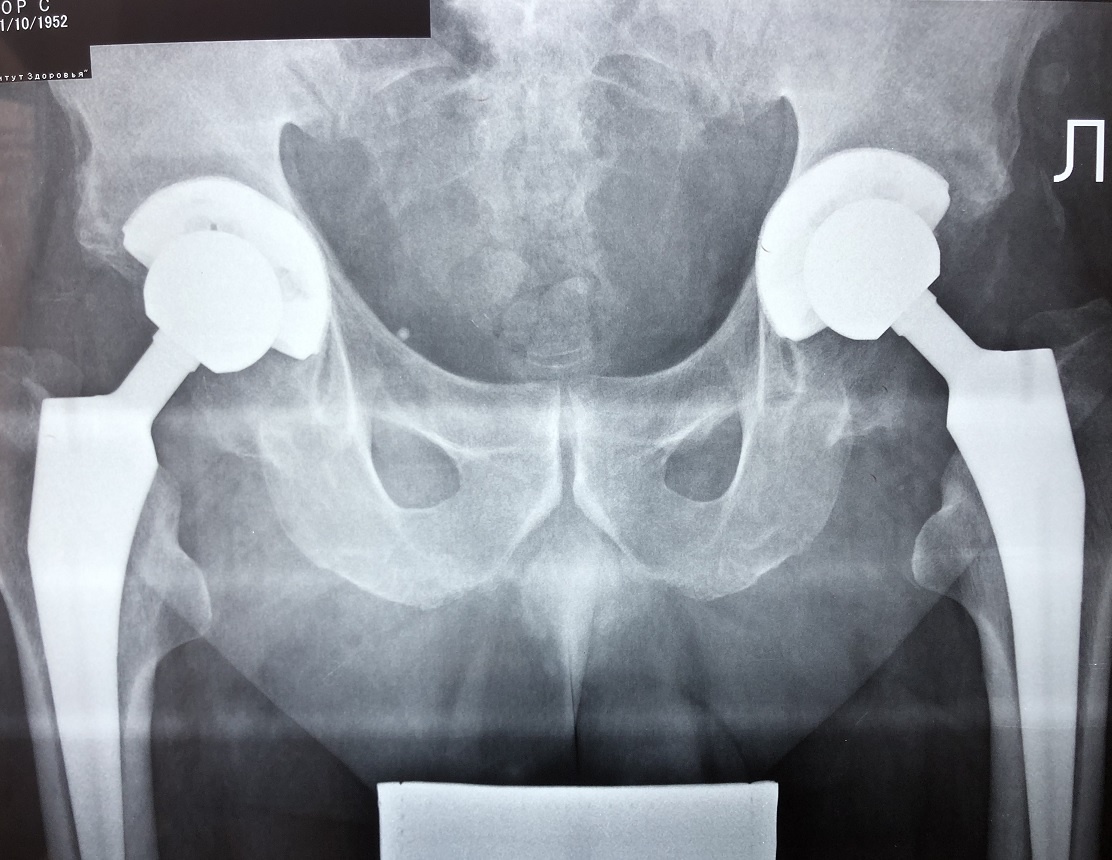

Двухсторонее протезирование тазобедренных суставов